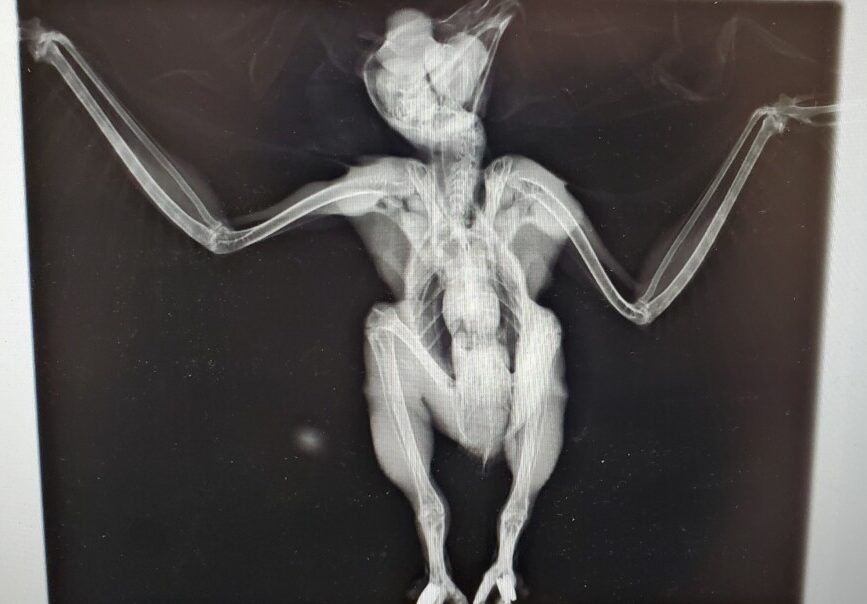

As a part of their diagnostic evaluation, the rehabilitation staff at VINS took some x-rays of Oberon that we thought we’d share with you — it isn’t every day you get to see the skeleton and musculature of an owl! This might help you visualize just how much of Oberon’s appearance is filled out with his insulating feathers